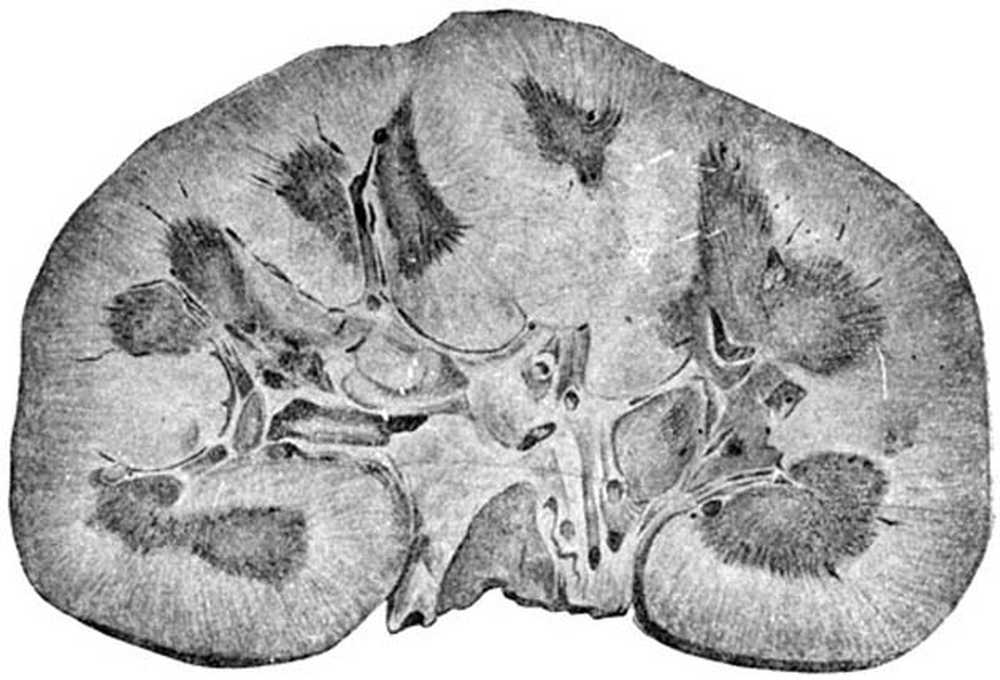

Симптомы подострого гломерулонефрита: фото и описание